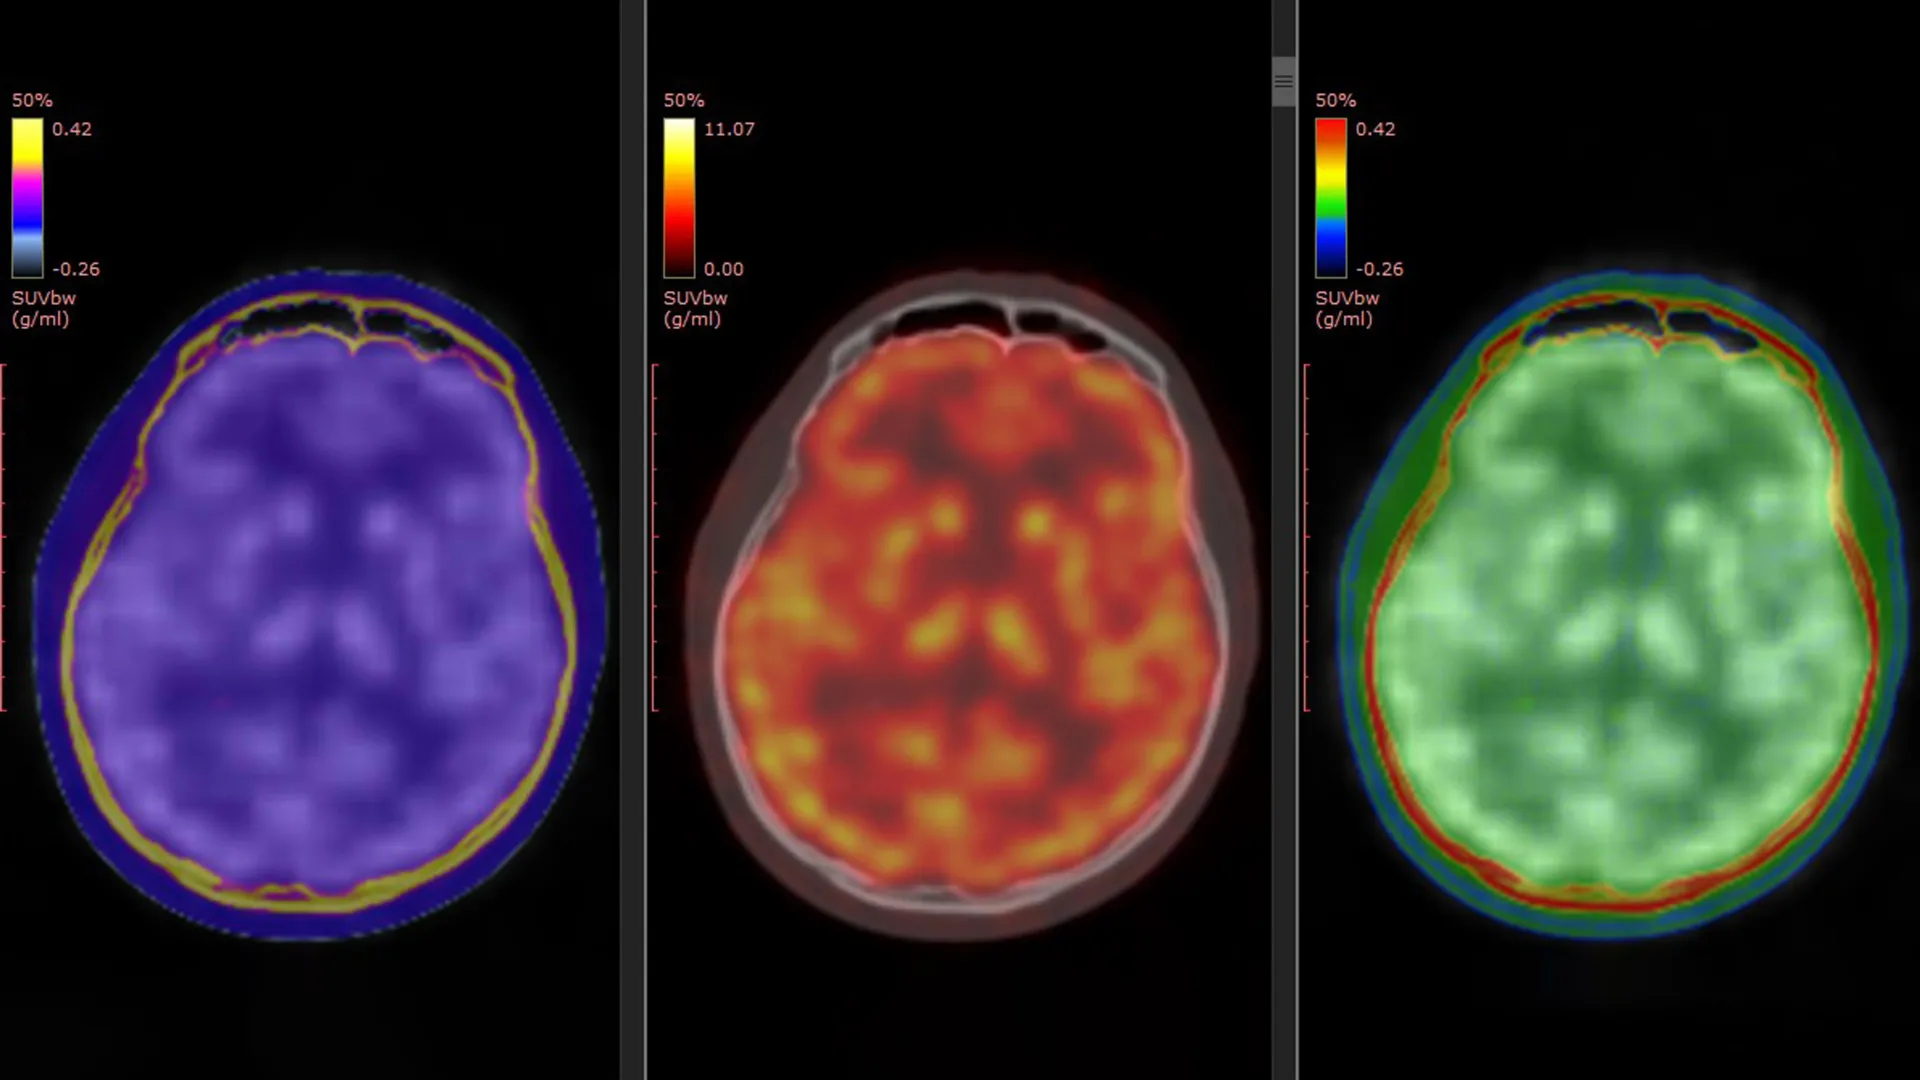

A groundbreaking study, published on March 5, 2026, in the esteemed journal Molecular Psychiatry, has significantly advanced our comprehension of this complex pharmacological puzzle. Spearheaded by Professor Takuya Takahashi of the Department of Physiology at Yokohama City University Graduate School of Medicine in Japan, the research team employed a cutting-edge positron emission tomography (PET) imaging technique to directly visualize alterations in glutamate $alpha$-amino-3-hydroxy-5-methyl-4-isoxazole propionic acid receptors (AMPARs). These receptors are critical protein components that govern neuronal communication and play a pivotal role in synaptic plasticity and glutamatergic signaling—processes that are profoundly affected in patients undergoing ketamine treatment.

The cornerstone of this pioneering research was the utilization of a novel PET tracer, designated as [11C]K-2, developed by Professor Takahashi’s team. This sophisticated tracer possesses the unique capability to visualize cell-surface AMPARs directly within the living human brain. Prior experimental and preclinical studies had strongly suggested a role for AMPAR activity in mediating ketamine’s antidepressant effects. This new investigation transcends those hypotheses by offering direct empirical validation in human subjects.

Participants diagnosed with TRD were administered either intravenous ketamine or a placebo over a rigorous two-week treatment period. To capture the dynamic effects of the intervention, PET brain imaging was performed at two critical junctures: immediately preceding the commencement of treatment and again following the final ketamine or placebo infusion. This longitudinal imaging design enabled the researchers to precisely quantify and compare changes in AMPAR levels and their spatial distribution within the brain over the course of the study.

The comprehensive analysis of the PET imaging data revealed a compelling pattern of AMPAR distribution in individuals with TRD. Specifically, the study identified widespread abnormalities in AMPAR density when compared to their healthy counterparts. Crucially, these observed differences were not diffuse across the entire brain but were concentrated within distinct, anatomically defined brain regions.

Furthermore, the administration of ketamine did not elicit a uniform effect on AMPARs throughout the brain. Instead, the improvements experienced by patients in their depressive symptoms were intricately associated with dynamic, region-specific modulations of AMPAR levels. In some cortical areas, researchers observed an increase in AMPAR density, suggesting enhanced neuronal signaling. Conversely, other regions, particularly those implicated in reward processing such as the habenula, showed a reduction in AMPARs. These nuanced, localized shifts in AMPAR distribution were found to be strongly correlated with the degree of symptom amelioration experienced by the patients.

"Ketamine’s antidepressant effect in patients with TRD is mediated by dynamic changes in AMPAR in the living human brain," Professor Takahashi elaborated. "Using a novel PET tracer, [11C]K-2, we were able to visualize how ketamine alters AMPAR distribution across specific brain regions and how these changes correlate with improvements in depressive symptoms."